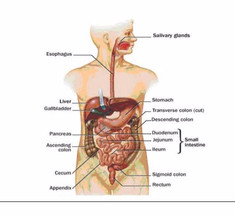

Упражнения, которые помогут наладить работу пищеварительной системы

Экология здоровья: Наиболее важной причиной запора является недостаток физических упражнений. Из-за этого снижается...